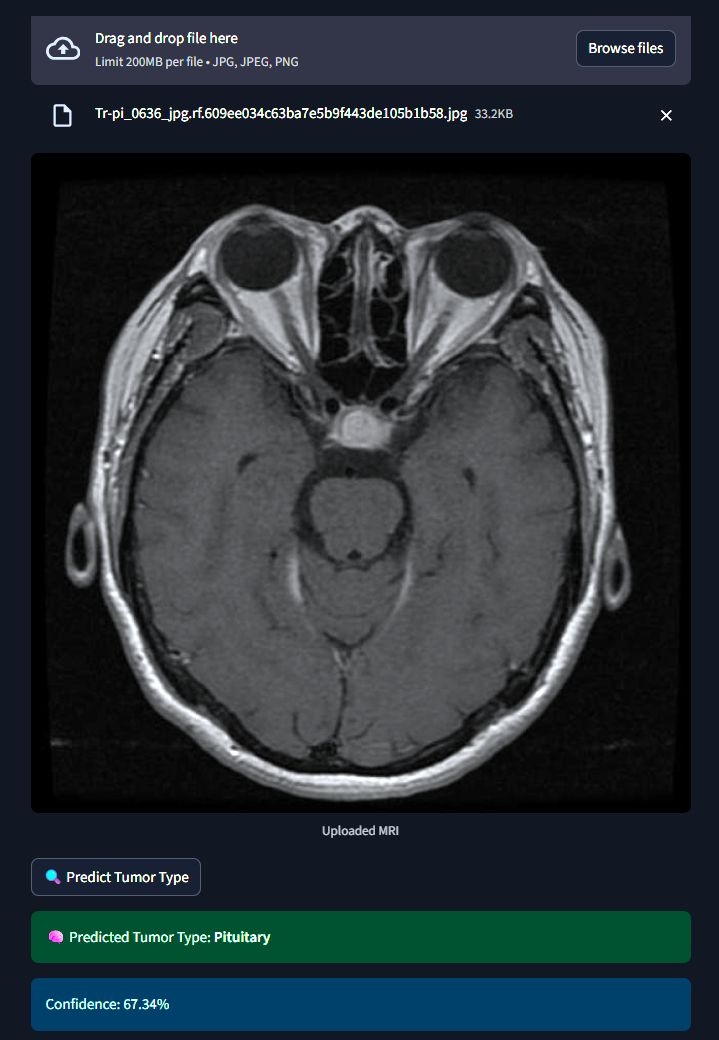

The system classifies MRI brain scans into one of four categories - Glioma, Meningioma, Pituitary Tumor or No Tumor. It uses both a Custom Convolutional Neural Network (CNN) and MobileNetV2 Transfer Learning for classification. An interactive Streamlit web app allows users to upload MRI images and receive real-time tumor predictions with probability scores.

1) Dataset :- 2,443 MRI images labeled and categorized by medical experts. 2) Preprocessing :- Used ImageDataGenerator for rescaling, rotation, zoom and flipping to augment limited data. 3) Model 1 (Custom CNN) :- Built from scratch with 3 convolutional layers, dropout and softmax classification. 4) Model 2 (MobileNetV2) :- Fine-tuned transfer learning model using pretrained ImageNet weights. 5) Training :- Used callbacks like EarlyStopping and ModelCheckpoint to optimize training and avoid overfitting. 6) Evaluation :- Tracked model performance using confusion matrix, accuracy/loss plots, and classification reports. 7) Deployment :- Developed a Streamlit web app for real-time image classification and visualization.